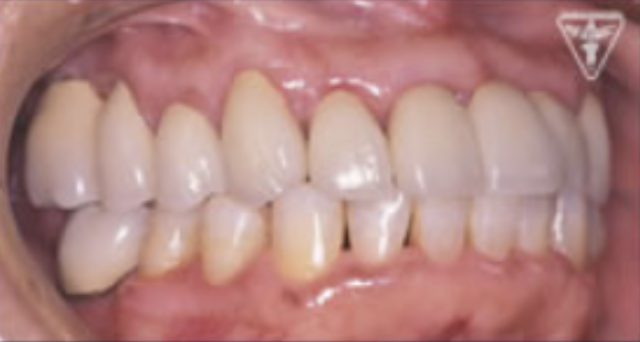

治療後

治療前後の比較

治療前